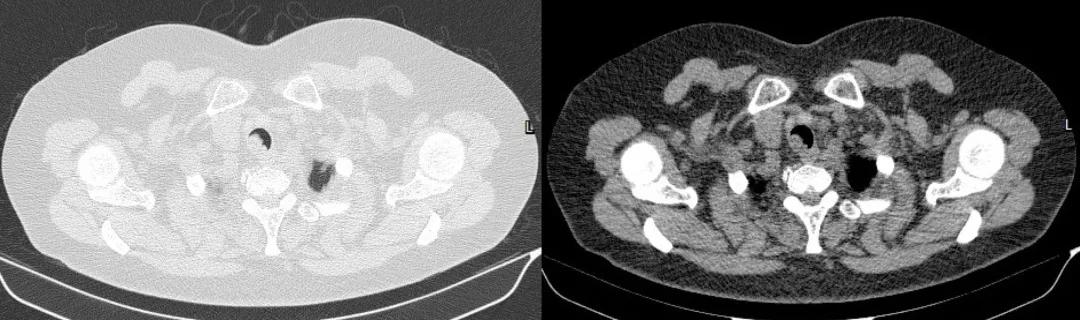

胸部CT:

胸部CT(横截面)

四、影像学检查:表现为气管腔内的软组织密度肿块

表现为气管腔内的软组织密度肿块,多为偏心性,好发于气管后壁、气管软骨,低中度均匀强化,伴气管壁增厚,管腔不规则狭窄。有时可见气管旁淋巴结肿大,提示肿瘤转移可能。晚期可血行转移至肺、骨、脑、肝脏。